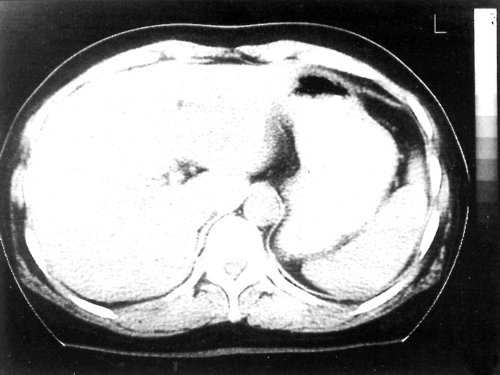

В нашем случае при ультразвуковом исследовании брюшной полости выявлено атипичное строение гемангиомы, динамическая компьютерная томография указывает на типичную гемангиому (рис. 2а, б). При этом важно знать, что только приблизительно в 54% случаев у больных с гемангиомами имеет место характерная перфузия с центростремительным усилением и поздним заполнением [20]. Однако в связи с тем, что этот тип усиления встречается только у 1,6% первичных и вторичных злокачественных опухолей печени, определение структуры данного усиления позволяет уверенно дифференцировать гемангиомы от злокачественных печеночных опухолей [20].

Рис. 2. КТ печени.

а) До контрастирования - в левой доле печени видно большое образование округлой формы.